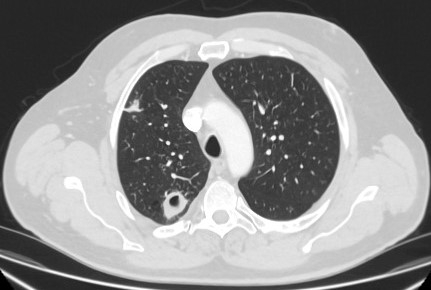

Cortes de tomografia computadorizada (TC) de dois casos com nódulos perifissurais benignos. Observe as margens lisas e a fissura adjacente normal e intacta

Do acervo de Dr. George Tsaknis, MD, PhD, FRCP (Londres), MRQA, MAcadMEd, PGCert; usado com permissão